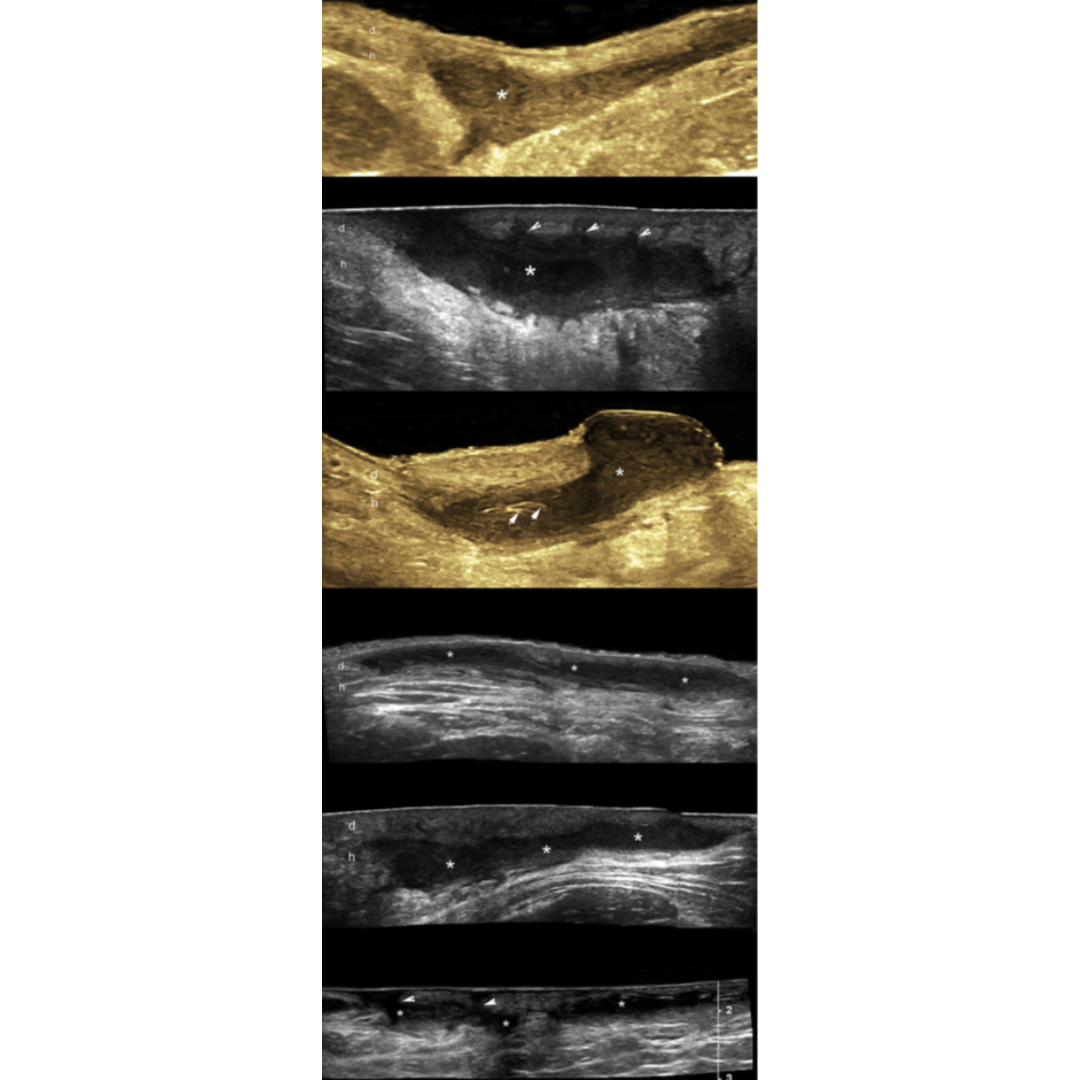

Figura 1: Imagen de ecografía de la región axilar que muestra el ensanchamiento de la parte superior de los folículos pilosos. (Signo de botella de Champagne)

Figura 2: Cambios dérmicos de la Hidradenitis Supurativa.

(*) Engrosamiento e hipoecogenicidad de la dermis

Piel normal: d: dermis h: hipodermis

Figura 3: Imágenes de ecografía con apariencia variable de fistula. Se observan conexión de las fistulas con la parte inferior de los folículos pilosos dilatados y los fragmentos lineales hiperecogénicos de tractos pilosos dentro de la fistula.

Figura 4: Hidradenitis supurativa de presentación variable, colecciones de líquido dérmico e hipodérmico. El asterisco señala las colecciones y las puntas de flecha apuntando hacia arriba indican los fragmentos lineales hiperecogénicos de los tractos pilosos dentro de la colección. Las flechas apuntando hacia abajo indican las conexiones entre las colecciones de líquido con los folículos pilosos dérmicos ensanchados.